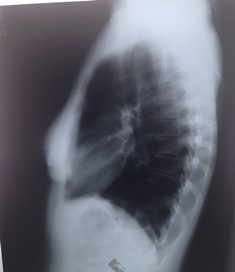

One day he told me he wanted to examine my lungs. He diagnosed a tuberculous legion in my left lung and recommended my discharge from the Army.

In Geneva I consulted a doctor, expecting to be sent to a sanatorium, but he found nothing wrong with my lungs. My chief must have deliberately misled the authorities out of compassion. As a chest specialist, which he was in civilian life, he could not have made a mistake.

Circumstances favoured me. Tuberculosis was rife at that time. To combat the spread of the disease, the government decided to open throughout the country tuberculosis treatment centres. I would be in charge of the one in Bialystok.